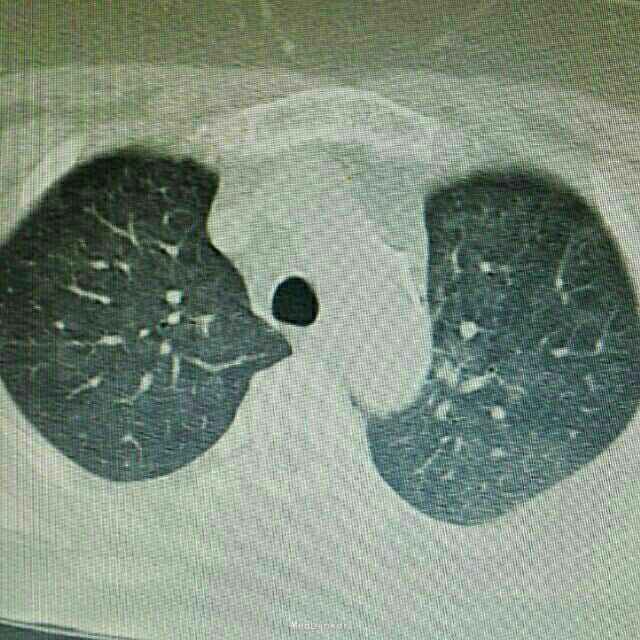

辅助检查:入院后行紧急胸部CT检查提示双肺弥漫性炎症改变,双下肺更加明显。

诊断:肺部感染,异体肾移植状态 治疗:根据胸部CT检查提示,真菌感染可能性大,给予科赛斯抗真菌治疗,加用舒普深抗细菌治疗。进一步检查生化、降钙素原、真菌D葡聚糖等炎性指标,监测患者体温、血气等指标。